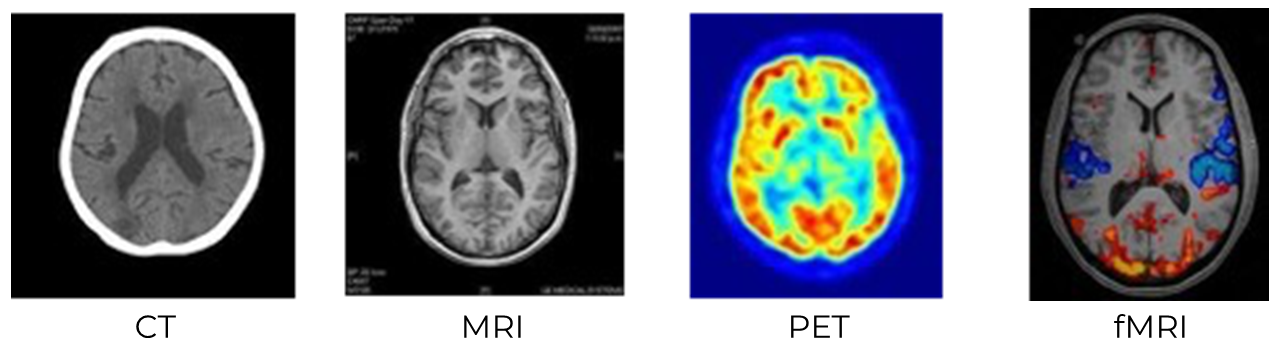

In order to activate students’ observational skills, ask them to analyze the images below of different technical brain imaging methods.

Explain that there are many different ways to get a visual representation of what is going on inside the head. Each method has strengths and weaknesses, and because of this, certain methods are typically used in certain settings.

Show students the images below and ask the the questions that follow:

- Which images are the sharpest? Which are the fuzziest?

- Which images have intensity or color scales? What do you think the colors or intensities might signify in each image?

- Compare the CT/MRI images with the PET/fMRI. What differences and similarities do they see between these groups?

- If students point out that MRI and fMRI look sharper than CT and PET, explain that the date of development of each technology correlates with the increasing image resolution. CT was introduced in the early 1970s, PET and MRI in the 1980s, and fMRI in the 1990s. Most present-day research in cognitive neuroscience uses fMRI when looking at brain activity for this very reason.

- If students point out that CT doesn’t show the difference between the white matter and gray matter within the brain, you can explain that this is why CT is not commonly used for neuroscience experiments but is often used by doctors and hospitals to see the location of tumors or areas of damage within the brain. Refer to Unit 1, Lesson 5 for more on gray and white matter.